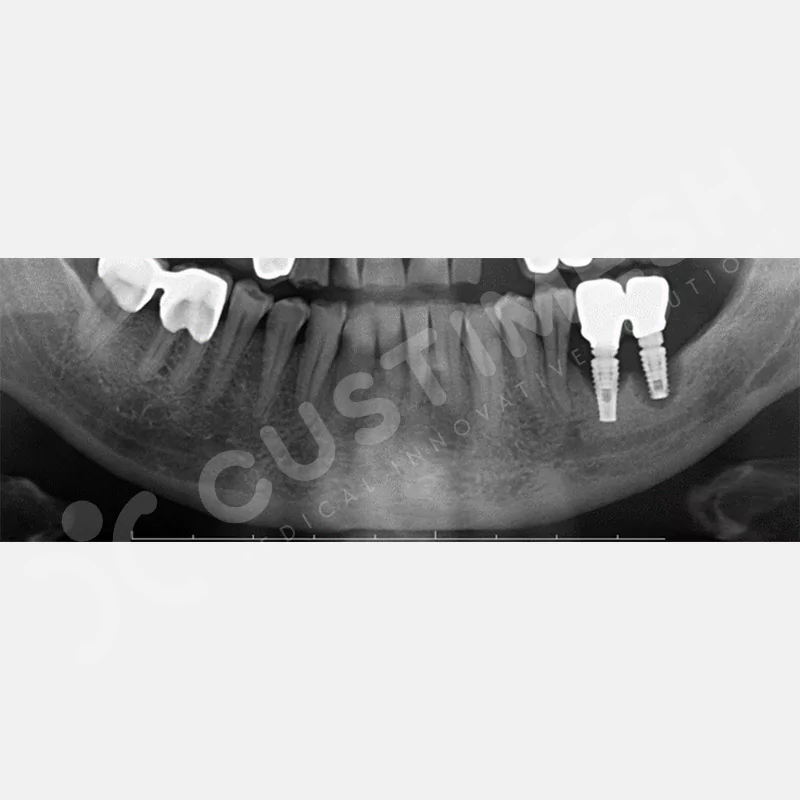

VAKA 1

VAKA 2

VAKA 3